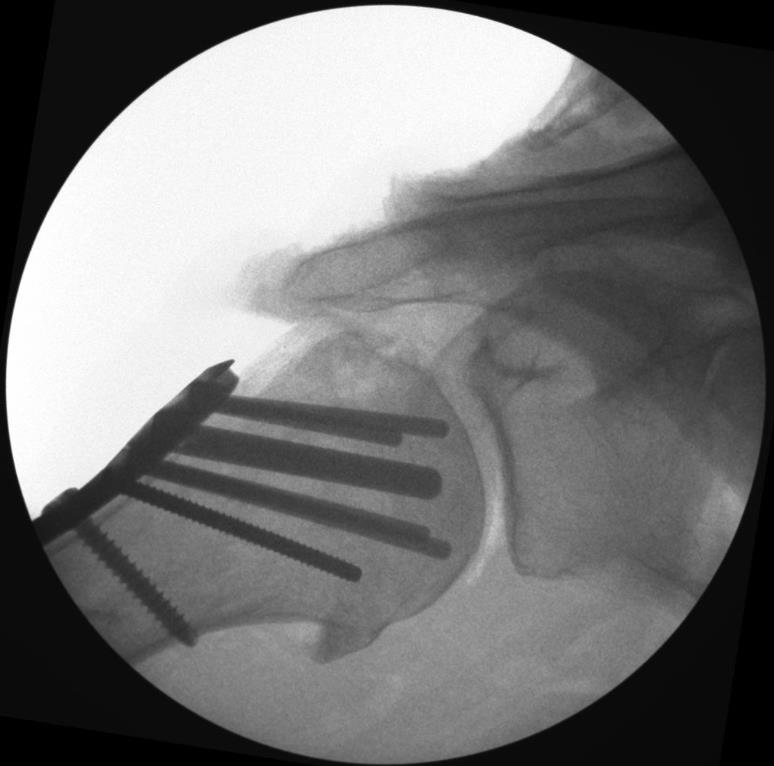

Proximal Humerus Fixation System

• The Proximal Humerus Fixation System (PHFS) from Skeletal Dynamics is a plate-and-peg/screw construct designed around proximal humeral anatomy for fixation of fractures, fracture-dislocations, osteotomies, and non-unions of the proximal humerus.

• The system centers on a proximal humerus plate with smooth locking pegs, locking/compression screws, and a central fixed-angle peg, with both straight and curved plate options.

• the PHFS has multiple, divergent, fixed-angle pegs oriented toward the humeral head dome to achieve broad subchondral spread and support the articular surface, with the goal of resisting varus collapse.

• Fluoroscopy in AP and lateral views is used to verify that the wire is center–center and follows the desired 135 degree trajectory.

• Final fluoroscopy confirms reduction, peg and screw lengths, plate height relative to the greater tuberosity, and absence of joint penetration or subacromial impingement risk.